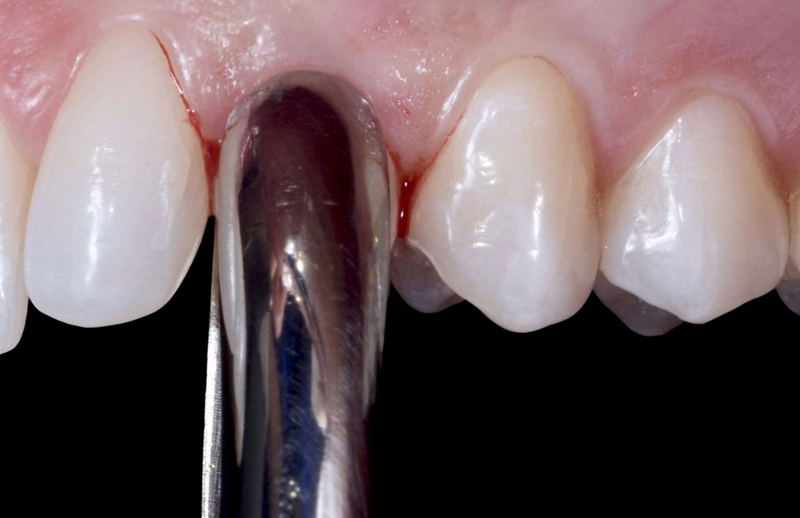

尽管可用骨量减少,但种植体稳定性仍可能达到 35n/cm 的扭矩值,这使得可以立即放置假体(图 40)。将直径为 3.8 毫米、牙龈高度为 1.5 毫米的定制临时基台用螺钉固定在种植体顶部(图 41)。然后,用棉球保护临时基台的烟囱,以避免在后续步骤中堵塞螺钉的入口。然后将临时牙冠放入透明面罩内;在用树脂填充牙冠后,通过透明面罩将其固定到位,以便与临时基台连接。树脂聚合后,拧下临时牙冠(图 42),牙冠和基台之间的空间填充树脂,然后进行调整,直到获得适当的紧急轮廓(图 43)。

Fig. 40: Despite the reduced amount of available bone, it was possible to reach a 35 n/cm torque value for the implant stability...

Fig. 41: The provisional abutment, shortened and sandblasted by dental lab, was...

Fig. 42: After resin polimerization, the temporary crown was...

Fig. 43: Image of the crown once screwed on the analog, vestibular side.

调整后,将临时牙冠放置在患者口腔中(图44),并拍摄术后X射线图像,以确保种植体和临时修复体的精度(图45)。

Fig. 44: After the refinements, occlusion was checked in the...